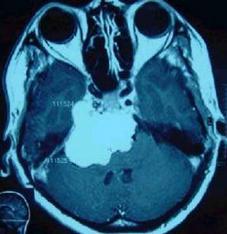

前面我们讲过,引起面肌痉挛的主要原因就是颅内的血管压迫面神经或者是颅内的占位性病变(肿瘤、炎症、囊肿等)压迫面神经导致,这个时候做磁共振就能够清清楚楚的发现颅内的病变。

比如这一副图,我们从磁共振上可以看到有一块巨大的肿瘤(白色高亮区域),这就是肿瘤引起的面肌痉挛。